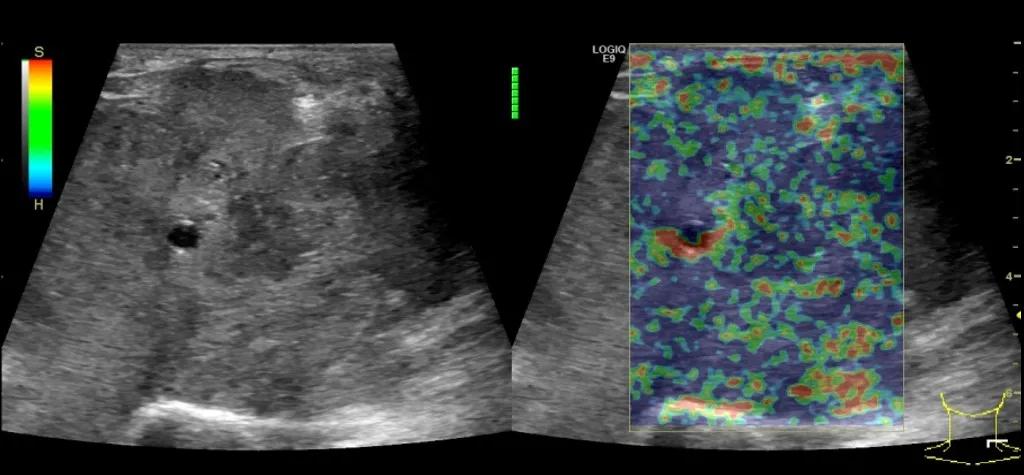

第四例是胸腺癌化妆包,术后、化疗之后淋巴结转移,肿块范围巨大,99mm*61mm,边界不清,呈浸润状,肿块包绕颈动脉,颈内静脉压闭,症状明显。由于患者放化疗也不敏感、血供非常丰富,于是采取多点姑息性消融。姑息性消融后未实现完全消融,病灶大片坏死,肿胀疼痛得到明显的缓解,后续患者未再来复查。

(病例4图例)